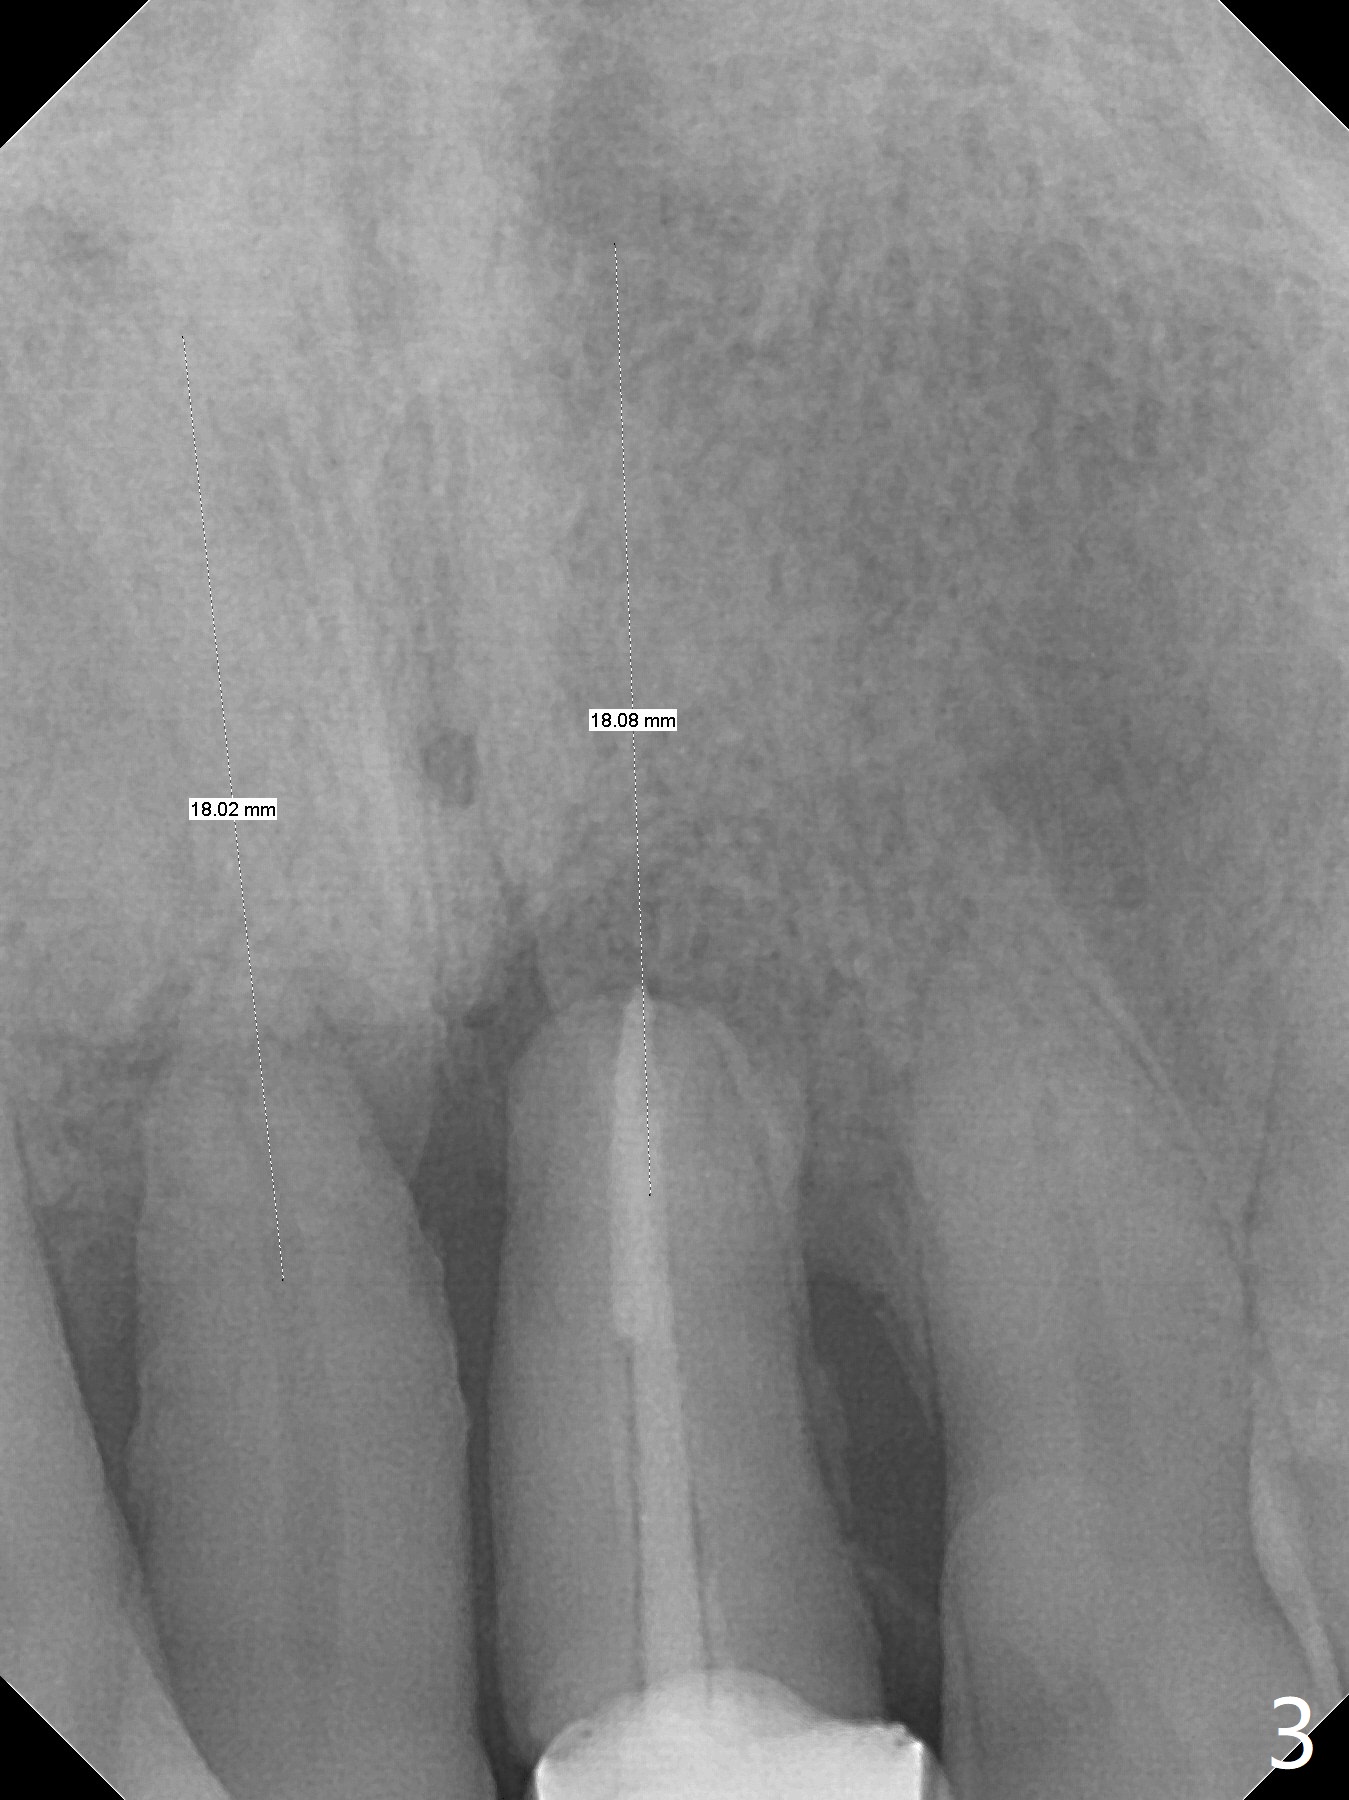

A 59-year-old man requests treatment for buccally displaced upper central incisors (Fig.1,2). It appears that the buccal plate is lost, but the bone height will allow placement of 3.5x13 mm implants with guide (Fig.3). Because of severe infection apical to the tooth #8 (Fig.4,5 *) and truncation of the incisal edges of the upper central incisors during CBCT taking (Fig.6,7 *), guided surgery may not be appropriate. The mesial surfaces of the teeth #7 and 10 and the incisal edges of the lower incisors (*) will be trimmed for immediate provisional. Immediate implants will be placed in the palatal crest of #8 (Fig.6 <) and close to the palatal crest of #9 (Fig.7). Angled abutments are expected (4.5x15 degree, A or B (4 mm cuff). PRF is to be preparedx2 (one for membrane; the other for sticky bone). Take Alginate impression when the patient returns for surgical stent.